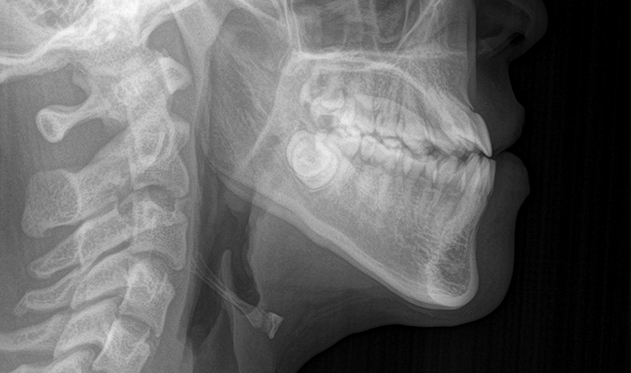

• 3Dデジタル診断と、

患者様ごとのシミュレーション